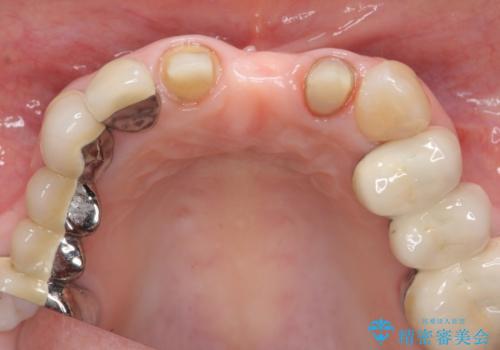

歯肉縁下カリエスも認められるため、挺出を行いセラミックブリッジを審美的に新製します。

- 47万円(仮歯×3・ファイバーコア×2・ジルコニアクラウン×3 歯の挺出)費用は治療当時の料金となります

虫歯が深くなった場合、挺出や歯周外科を行い歯周組織の状態を改善することでより安定した状態で予知性の高いセラミックブリッジを製作することが可能となります。